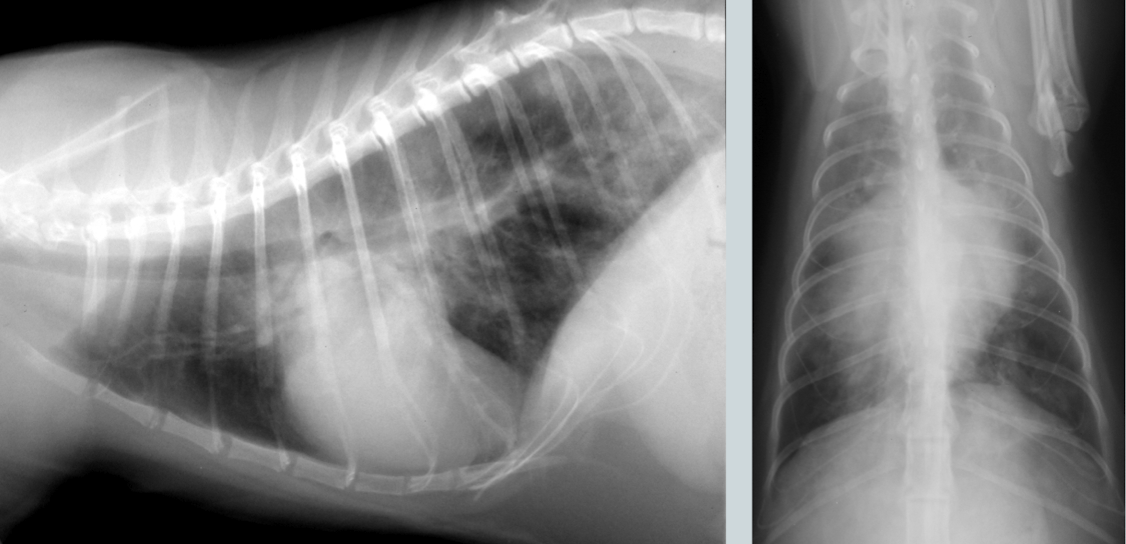

General condition?

Atelectasis

note the mediastinal/cardiac shift to the right and the soft tissue opacity of right middle lung lobe

What condition?

Atelectasis secondary to pneumothorax

note: retraction of lung lobes from thoracic wall and soft tissue opacity of left and right middle lung lobe